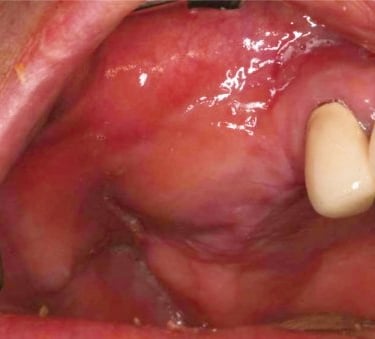

Edentulismo completo

El edentulismo completo es la ausencia total de dientes en una o ambas arcadas.

Los pacientes tienen dificultad para masticar, hablar y pueden sentirse incómodos con su apariencia.

El tratamiento puede incluir la colocación de una prótesis completa sobre implantes, proporcionando una solución fija y estable